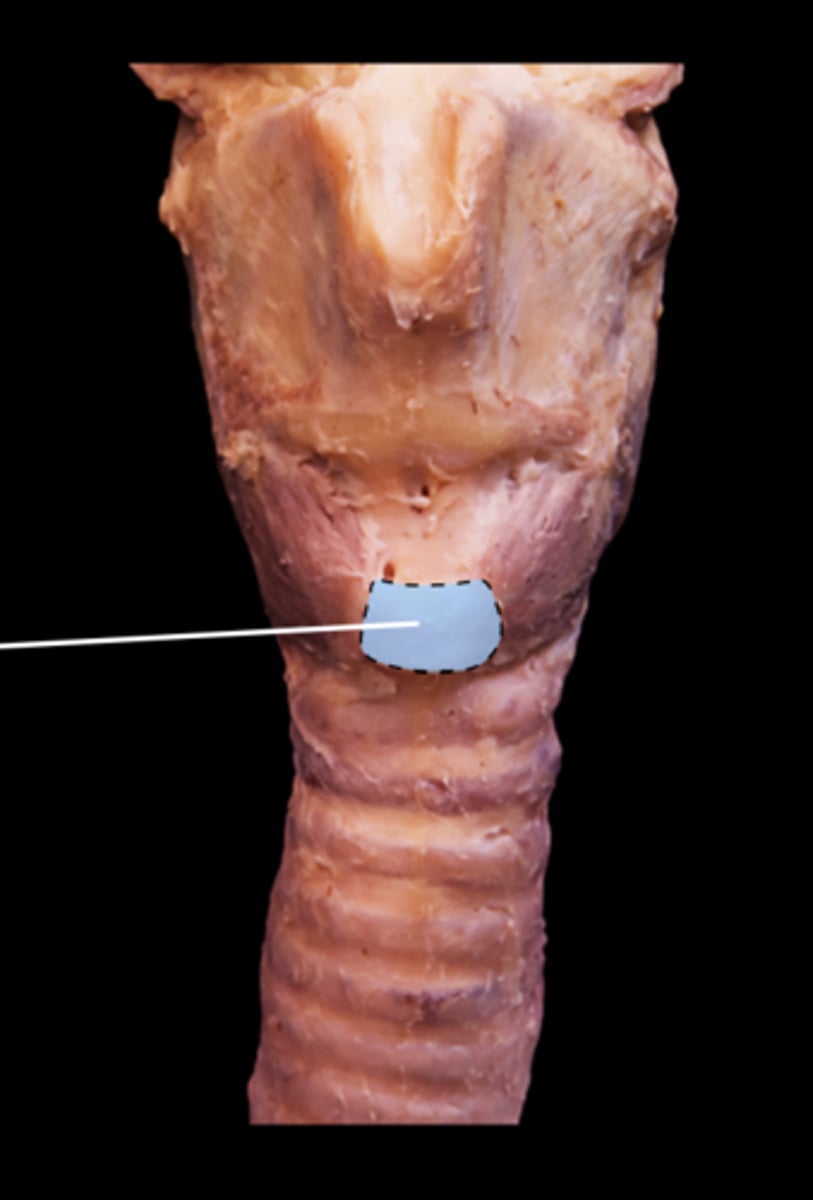

Thyroid Cartilage of Larynx

Cricoid Cartilage of Larynx

Trachea